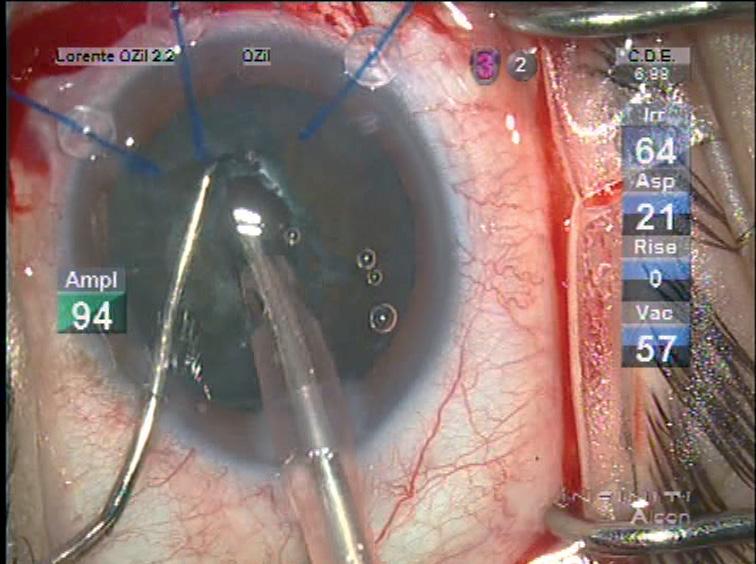

Cataract surgery in eyes with pseudoexfoliation can be very stressful, but there are many tools and techniques available to deal with its principal difficulties such as poor pupil dilation, and more important progressive zonular dehiscence preoperatively intraoperatively and postoperatively, reports Betty Lorente MD, FEBO, University Hospital, Ourense, Spain.

“The goal is to maintain the capsular bag in place to avoid inflammation through excessive manipulation, minimising complications and implant the lens in a safe position,” Dr Lorente told the 24th ESCRS Winter Meeting in Marrakech, Morocco.

She noted that in her region the rate of PEX among patients scheduled for cataract surgery is particularly high at 22% among those over 70 years and 33% among those over eight years. She added that every case of pseudoexfoliation is different and she presented the set of guidelines used at her centre to deal with most types of cases.

In eyes with PEX, the cataract surgeon should also be prepared with adequate tools for miosis, every degree of nuclear hardness and zonular weakness, she said. For example, she noted that she always likes to keep diluted triamcinolone at hand in case an anterior vitrectomy becomes necessary. It not only helps visualise any vitreous brand but also has an antiinflammatory effect postoperatively.

PUPIL DILATION AND HYDRODISSECTION

In eyes with PEX, preoperative exploration is very important, the cataract procedure

begins before the patient enters the operating room, even before instillation of mydriatic drops, since phacodonesis is best observed in miosis. It is also important to look for indirect signs of zonular dehiscence such as an asymmetric anterior chamber depth, Dr Lorente said. She usually uses local anaesthesia, but peribulbar and sub-Tenons may be considered for cases requiring longer and more difficult cases. For pupil dilation, iris hooks – or capsular hooks – are the preferable tool in PEX cases, not only for

economic reasons but also because they can help stabilise the capsular bag during the surgery. Once the capsulotomy is completed, the hooks may then be moved to the capsular rim if necessary, to stabilise the bag during the phaco.